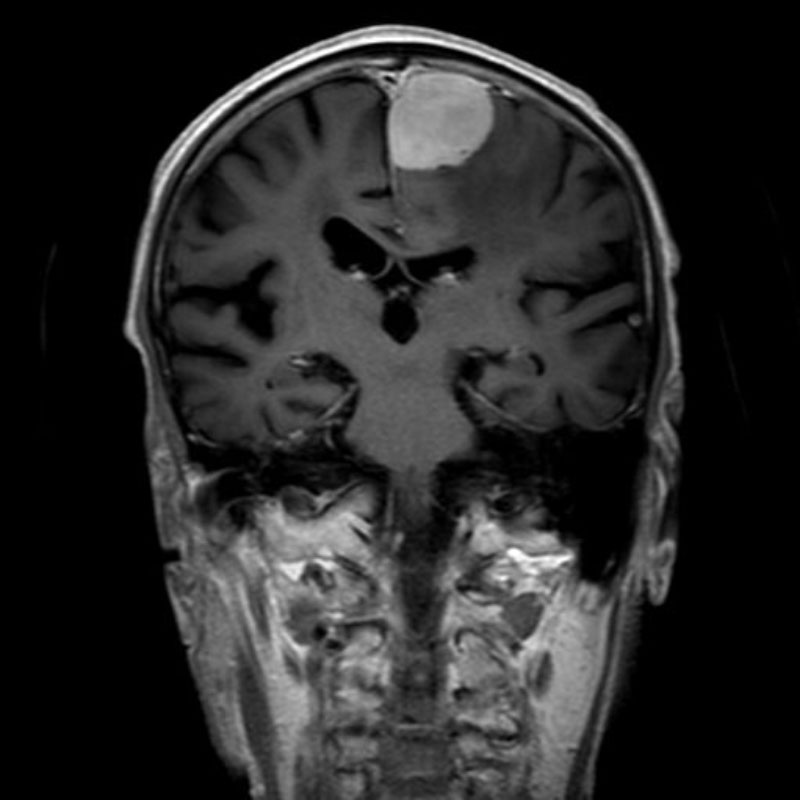

620

'25年4月

60代

円蓋部髄膜腫

頭蓋内腫瘍摘出術

No.’25_22 手術前1

No.’25_22 手術前2